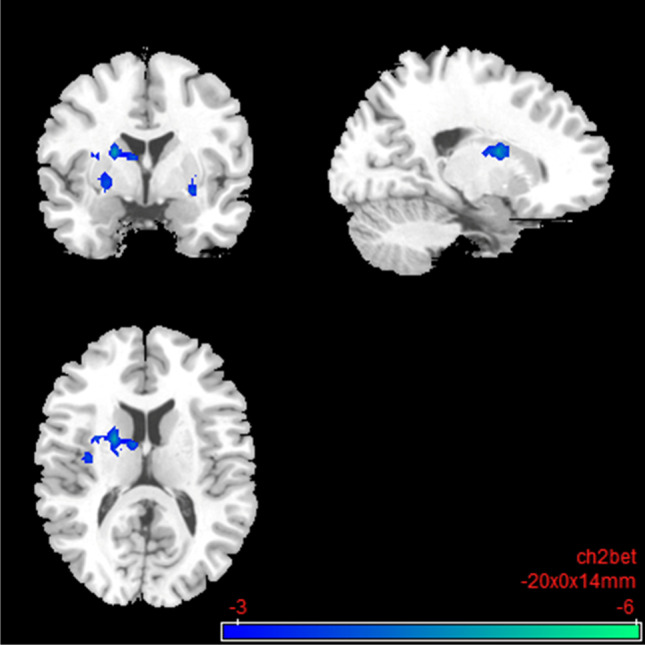

Compared to the placebo condition, the rsFC in the nalmefene condition showed reduced FC within elements of the impulsive system. There was decreased connectivity between the right Nacc and putamen, pallidum, caudate, thalamus, amygdala, and insula (Table 2; Fig. 6). The results also survived a more conservative voxel-wise threshold of p < 0.005 (please see Table S3; Fig. S4 in the Supplementary Information). No significant results could be detected for the left Nacc.

Fig. 6.

Impulsive system: brain regions with decreased resting-state functional connectivity between the seed region “right nucleus accumbens” and the rest of the brain after 18 mg nalmefene compared to placebo (contrast: nalmefene > placebo, MNI coordinates: − 20 00 14). Combined voxel-wise-threshold (p < .01) and cluster-extent threshold k > 460 Voxel, corresponding to pFDR < .05